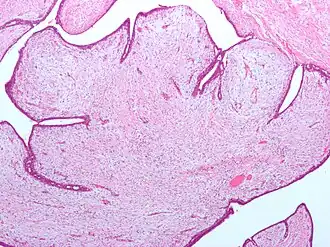

| Tumores filoides possuem grandes fendas e um estroma celular mixoide. Micrografia. Coloração H&E. | |

Tumor filoide (do Grego: phyllon folha), também conhecido como cistosarcoma filoide, é uma massa tipicamente grande, de crescimento rápido que se formam a partir das células estromais periductais da mama. Eles contribuem para menos de 1% de todas as neoplasias da mama.